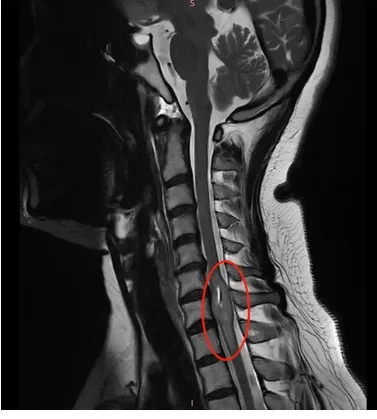

當檢查發(fā)現(xiàn)“頸7水平脊髓占位病變”,就是在是頸椎的第七節(jié)里面長了一個腫瘤時。我首先想到的是,這個要手術嗎?

影像